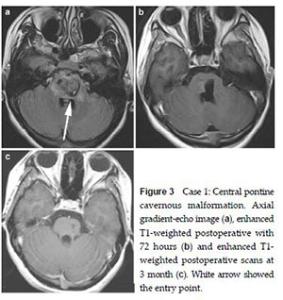

20170712151327 Figure 1 MRI demonstrated the typical “porpcorn” or “mulberry-like” BSCMs. (a), (b) and (c) showed one patient with pontine cavernoma. (d), (e) and (f) showed another patient with left cerebellar peduncle cavernoma. (a) and (d) axial T1-weighted, (b) and (e) axial T2-weighted, (c) axial enhanced T1-weighted, (f) SWI.